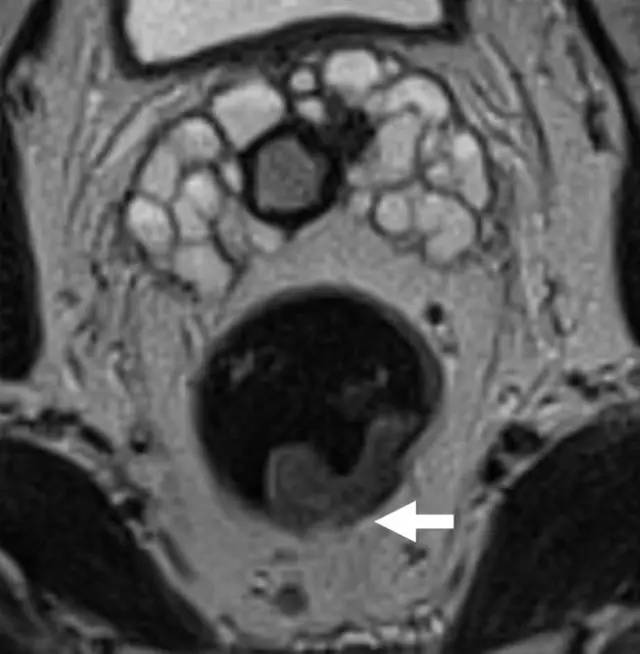

图 29 轴向 T2 加权图像报告 CRM 的距离。虚线描绘了直肠系膜筋膜,这是 T3a 肿瘤的 CRM,预测 CRM 阴性